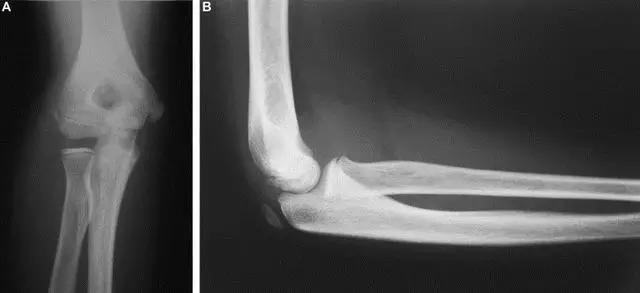

9. Monteggia 骨折(孟氏骨折)

尺骨近端 1/3 骨折合并桡骨头半脱位。

(来源:Radiopaedia)

成人 Monteggia 骨折

儿童 Monteggia 骨折